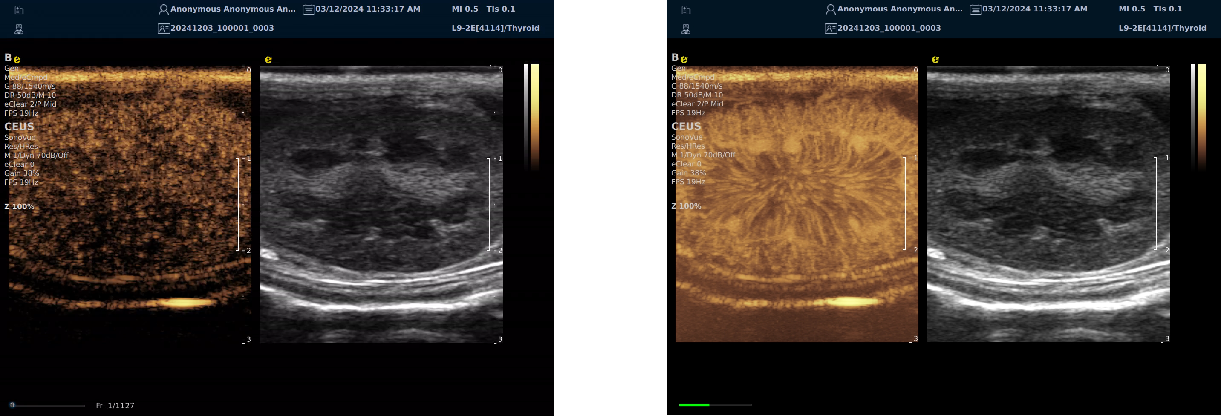

平面波超微细血流显像

能够提供更多真实的组织细小及末梢血管的血流信息,直观的观察组织内部的血管架构及血流形态的情况,提供临床更多有价值的诊断信息。

临床应用:

肿瘤鉴别诊断(肝脏、肾脏、甲状腺、乳腺、  涎腺等)

淋巴结评价(炎症、肿瘤)

肌骨系统临床诊断和疗效监测(关节、滑膜、韧带、肌肉炎症、 损伤等)

斑块内新生血管评估

超声介入术前进针方案提供血流参考信息

超声介入术后疗效评估

image.png